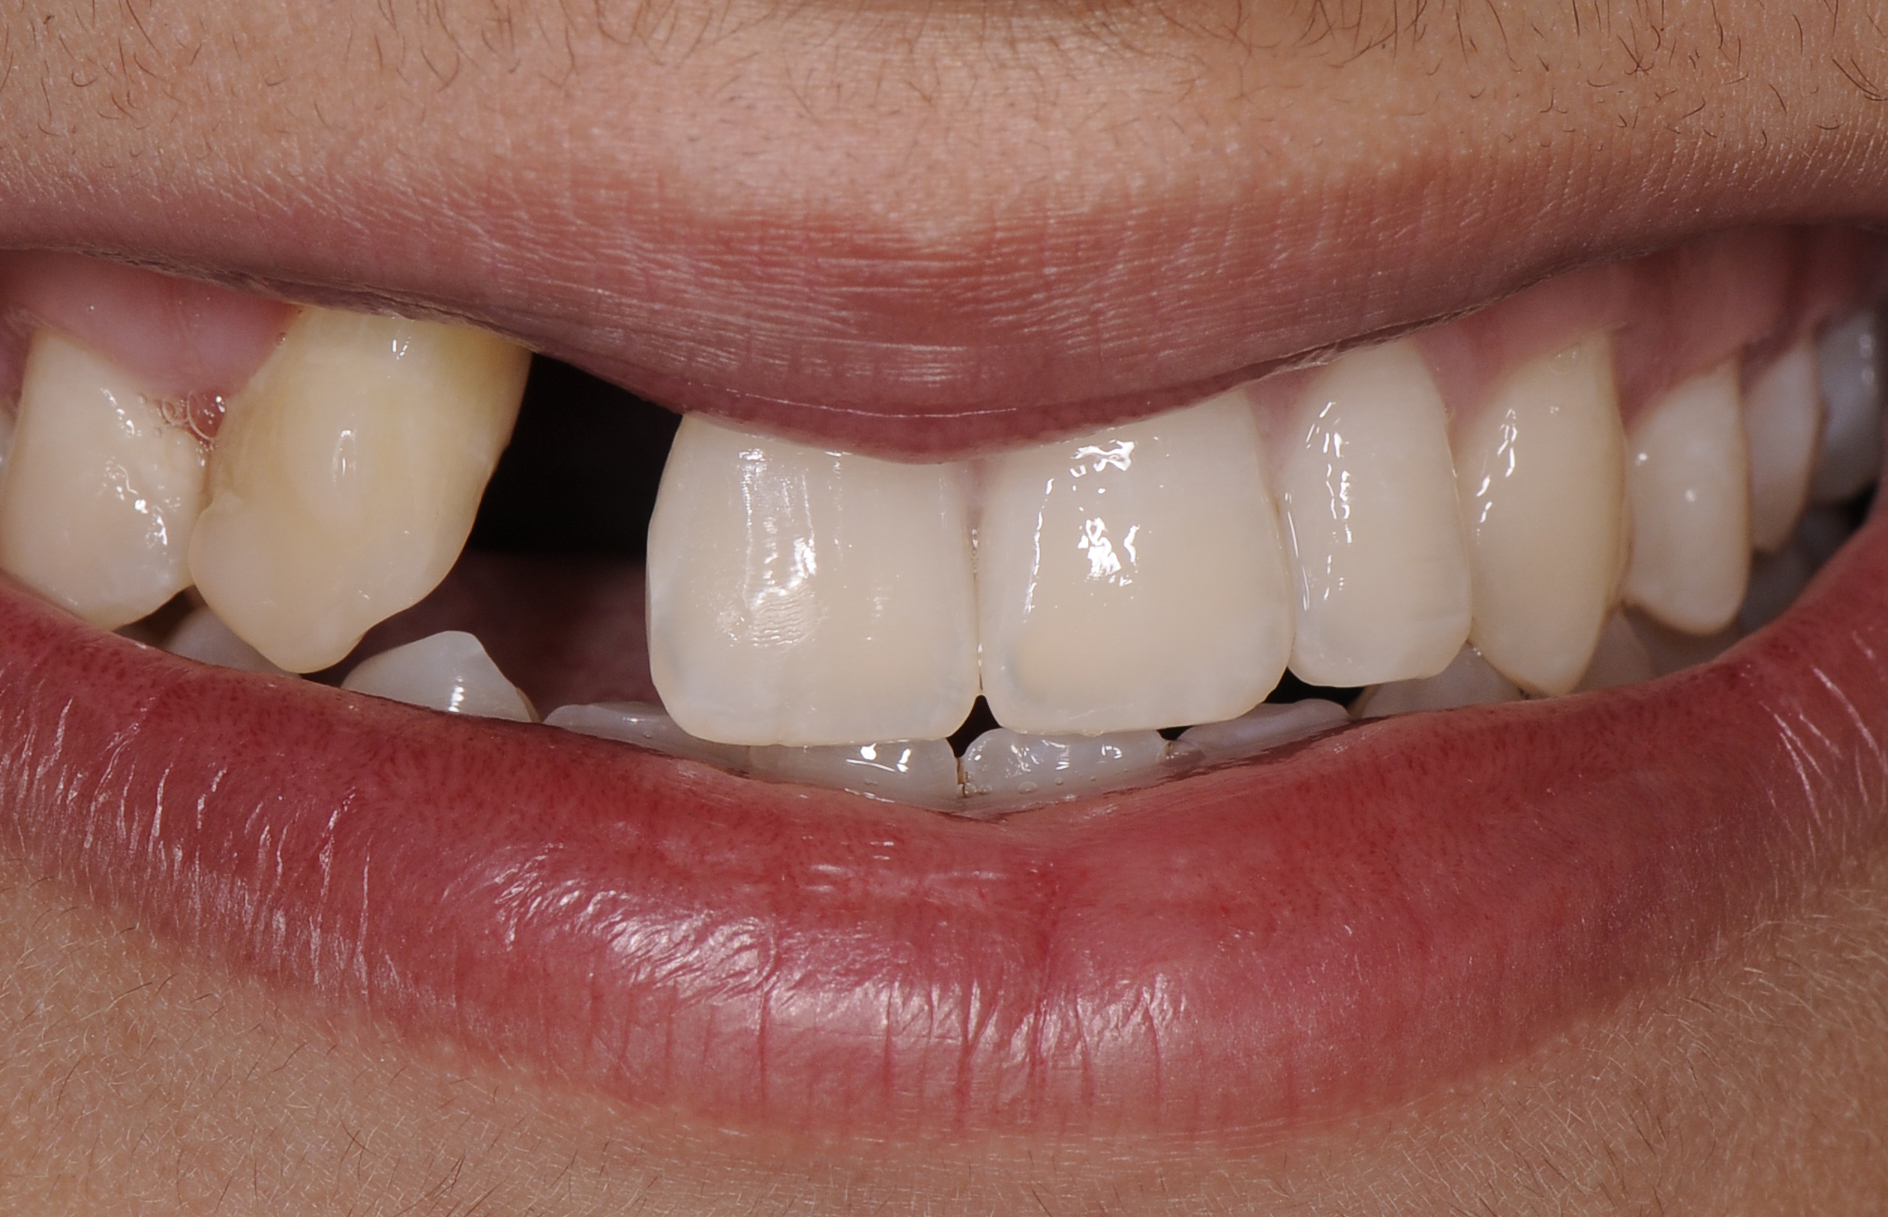

A healthy 20-year-old woman presented to the author’s office requesting treatment for a large defect in the area of missing tooth No. 7. She exhibited a high smile line that revealed a clearly visible deformity, associated with pain and sensitivity on teeth Nos. 6 and 8 and in the area of tooth No. 7 (Figure 1). Although the patient wore a modified Essix retainer, the defect was still visible because of the magnitude of tissue loss and the revealing nature of her smile.

Fig 1. The patient presented with a large deformity stemming from a congenitally missing maxillary right lateral incisor.

Figure 1